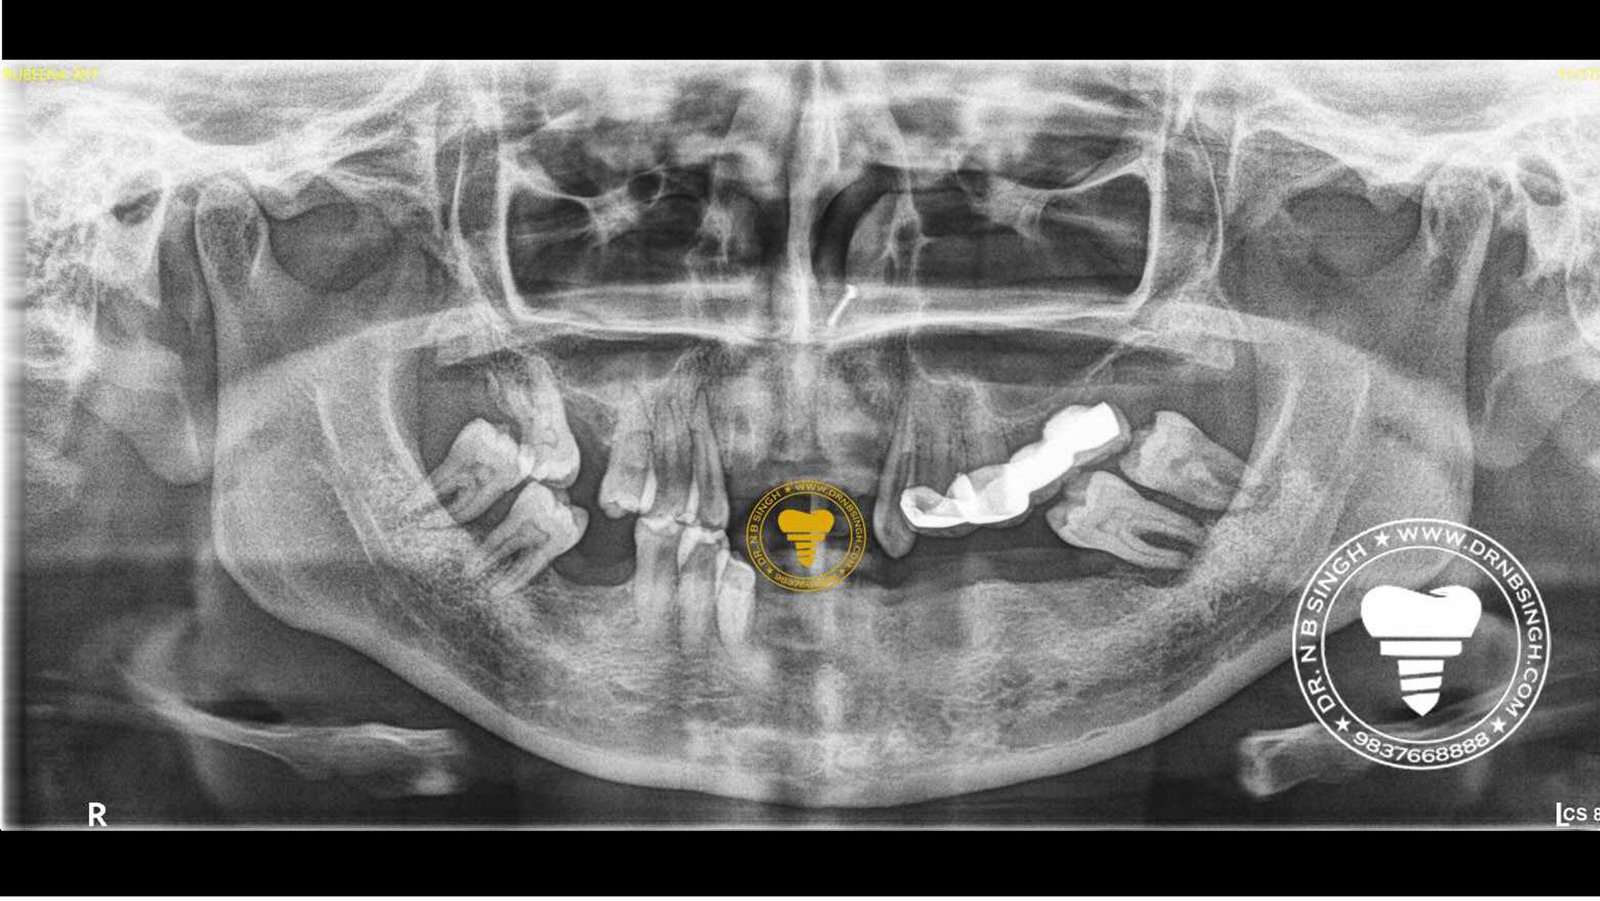

1002 Basal Full Mouth Implants Case Rubeena 2

1002 basal implant full mouth case rub 4